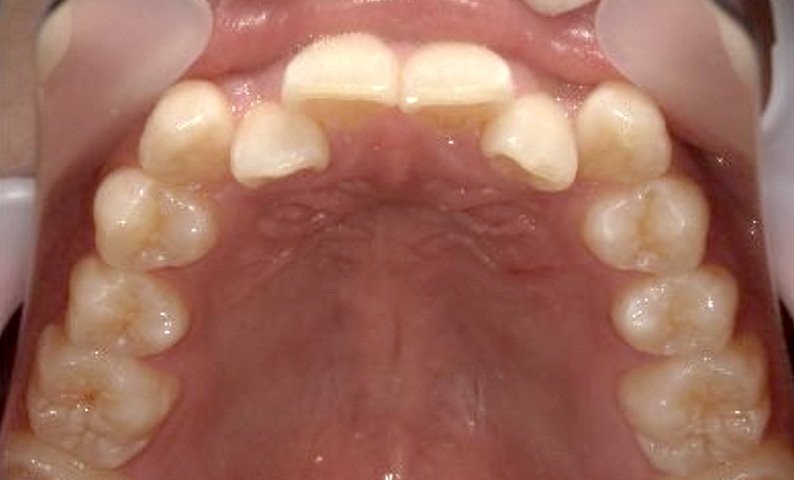

症例_024 上顎だけの部分矯正

治療期間:7ヶ月金額:30万円+税女性前歯のガタガタ上の前歯だけ